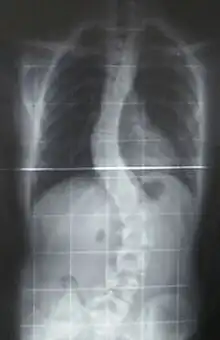

When scoliosis is suspected, weight-bearing, full-spine AP/coronal (front-back view) and lateral/sagittal (side view) X-rays are usually taken to assess the scoliosis curves and the kyphosis and lordosis, as these can also be affected in individuals with scoliosis. Full-length standing spine X-rays are the standard method for evaluating the severity and progression of scoliosis, and whether it is congenital or idiopathic in nature. In growing individuals, serial radiographs are obtained at 3- to 12-month intervals to follow curve progression, and, in some instances, MRI investigation is warranted to look at the spinal cord.[80] An average scoliosis patient has been in contact with around 50–300 mGy of radiation due to these radiographs during this time period.[81]

The standard method for assessing the curvature quantitatively is measuring the Cobb angle, which is the angle between two lines, drawn perpendicular to the upper endplate of the uppermost vertebra involved and the lower endplate of the lowest vertebra involved. For people with two curves, Cobb angles are followed for both curves. In some people, lateral-bending X-rays are obtained to assess the flexibility of the curves or the primary and compensatory curves.